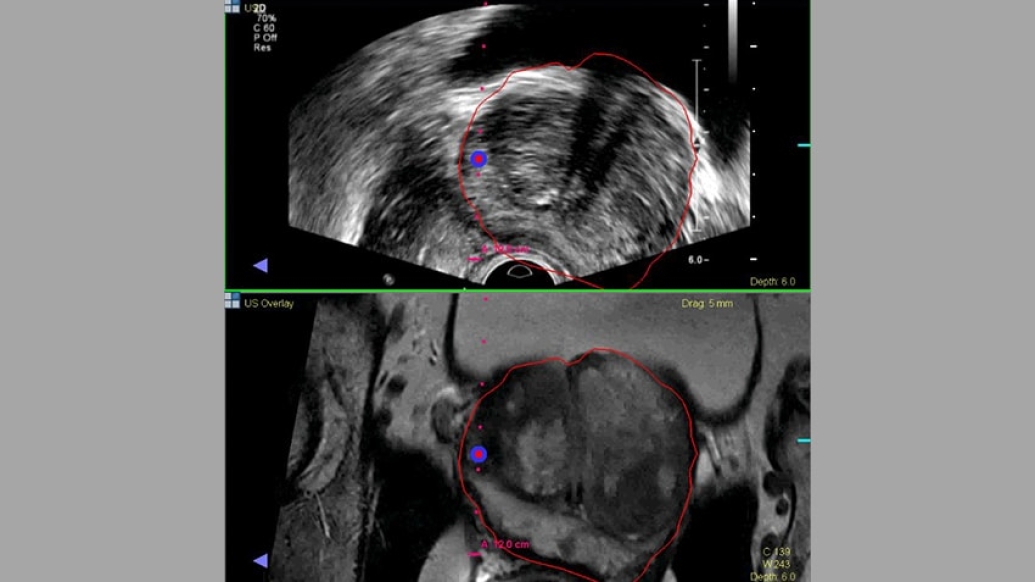

Palapattu compares it to shooting fish in a barrel with your eyes blindfolded. UroNav is like taking off the blindfold. (For example, the photo above shows an ultrasound image and then the fusion MRI/ultrasound image, which appears more clear and precise.)

The technology allows urologists to know where a suspicious lesion is so a biopsy needle can be targeted more precisely. In addition, the system can store the trajectory of needles so repeated biopsies can sample the same area. Michigan Medicine specialists used a similar system for research studies since 2012.